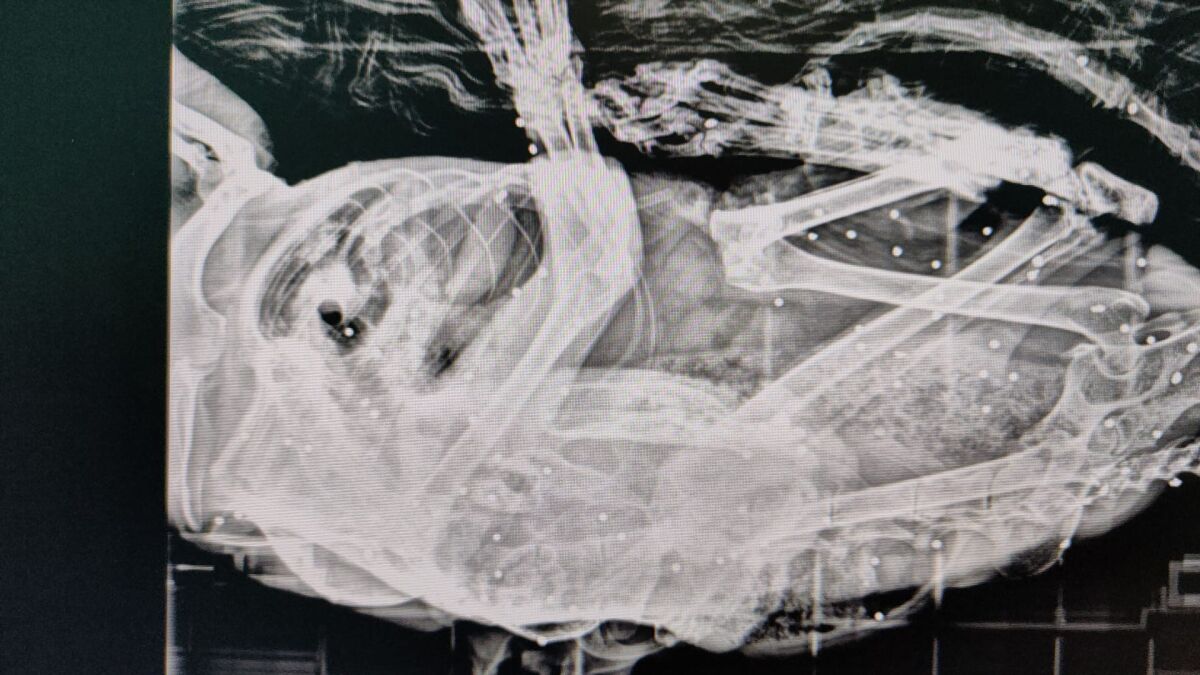

La asociación Gatucos Torrelavega ha atendido recientemente a un gato procedente de una colonia felina de Posadillo (Polanco) que albergaba más de 50 perdigones en su cuerpo. Se trata de Van Gogh, un animal que había sido intervenido quirúrgicamente por un carcinoma en la oreja y se encontraba recuperándose en el refugio cuando comenzó a mostrar cojera persistente. Tras su traslado al veterinario y la realización de pruebas radiológicas, se detectaron los perdigones en su interior.

"No estamos ante un hecho fortuito. Todo apunta a un acto deliberado, prolongado y con ensañamiento, ya que de haber sido un único disparo, el animal habría huido instintivamente. La acumulación de impactos solo puede explicarse por una acción consciente y reiterada de extrema crueldad", ha subrayado la entidad en un comunicado.